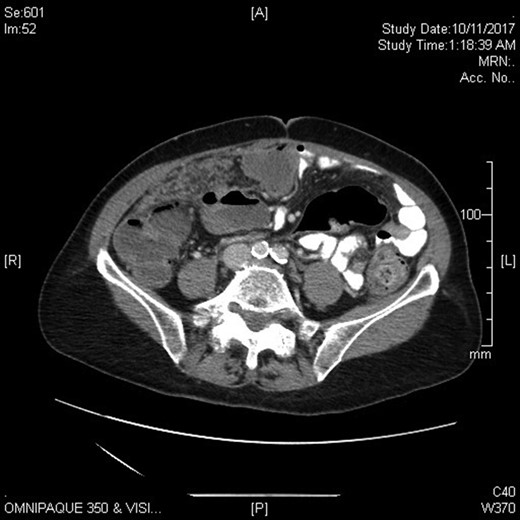

Physical examination revealed a markedly distended abdomen that was otherwise soft and non-tender. She had liver enzymes that were elevated two to five times the upper normal limit. Her tumour markers showed mildly elevated CA-125 and BetaHCG, but normal CEA, AFP and CA19.9. Computed tomography imaging revealed stigmata of chronic cholecystitis and a mass at the gallbladder fossa with evidence of hepatic and peritoneal metastases. The overall appearance was suggestive of metastatic gallbladder carcinoma, though primary hepatocellular carcinoma was considered a possibility given her past history of hepatitis C (Figs 1 and 2).